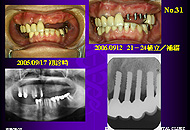

3)欠損歯数より少ない本数の植立:2症例 8本

3)直径3mm単独植立の症例:6症例 6本

欠損歯数と植立本数では「同本数」が多く、これが原則であると思う。 「多い本数」は右下765や左下567の3本欠損に3mmAQBを4本植立した場合や、近遠心径があって頬舌径が狭いため直径5mmAQBの植立ができないような右下6部に4MMと3MMを植立した場合が含まれる。 「少ない本数」は上顎前歯小臼歯部の5本欠損で、切歯管部位の植立を避けたため、3mmAQBを4本植立した場合である。

また複数本植立が原則で、「すべて直径3mm」は植立部位の骨幅が全域にわたって 狭い場合で、「直径4または5mmを含む」は幾分骨幅が広い部位に直径3mmより太いものを同時に植立できる場合である。 「直径3mm単独」は極力避けたい症例であることに間違いない。